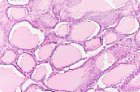

Диффузный токсический зоб классифицируется как первичная тиреоидная гиперплазия и гипертрофия. Поверхность железы гладкая, на разрезе ее вещество плотное, однородного строения, серовато-розового цвета, иногда блестящее или коллоидного вида. Могут встречаться мелкоточечные белесоватые включения (лимфоидные инфильтраты), очаги или прослойки фиброзной ткани. Гистологически мы различаем три основных варианта диффузного токсического зоба (базедовой болезни):

- коллоидный пролиферирующий зоб с морфологическими признаками повышения функции тиреоидного эпителия.

Первый вариант - классический. Для него характерна усиленная пролиферация тиреоидного эпителия с образованием сосочковых выростов в фолликуле, что придает им звездчатый вид. Фолликулярный эпителий обычно низкий, цилиндрический или кубический. Лимфоидная инфильтрация стромы выражена в различной степени, носит очаговый характер. При ее слабой выраженности очажки лимфоидных клеток локализуются преимущественно под капсулой. Существует прямая связь между степенью проявления лимфоидной инфильтрации и титром антитиреоидных антител, а также выраженностью онкоцитарно-клеточной реакции. В таких железах иногда отмечается развитие фокального аутоиммунного тиреоидита. В ряде случаев наблюдается исход диффузного токсического зоба (базедовой болезни) в аутоиммунный тиреоидит.

Второй вариант болезни встречается преимущественно у лиц молодого возраста. Гиперплазия тиреоидного эпителия выражена особенно сильно. Пролиферация тиреоидного эпителия сопровождается новообразованием мелких фолликулов, выстланных цилиндрическим и реже кубическим эпителием. Основная масса таких фолликулов содержит небольшие количества жидкого интенсивно резорбирующегося коллоида или лишена его. Располагаются фолликулы вплотную друг к другу. Это так называемый паренхиматозный тип строения железы.

Коллоидный пролиферирующий зоб в отличие от эндемического коллоидного зоба характеризуется усиленной пролиферацией фолликулярного эпителия с образованием либо многочисленных сосочковых выростов, либо сандерсоновских подушечек. Фолликулярный эпителий большей частью кубический, с морфологическими признаками повышения его функциональной активности. Коллоид в основной массе фолликулов жидкий, интенсивно резорбирующийся.